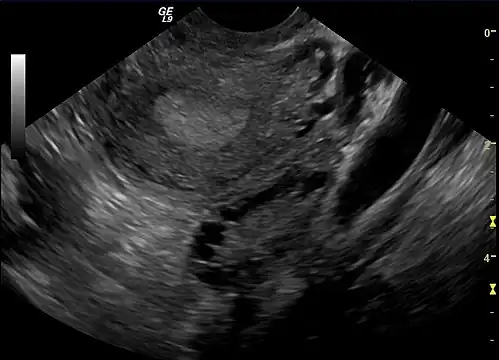

| A polycystic ovary | |

The syndrome acquired its most widely used name due to the common sign on ultrasound examination of multiple (poly) ovarian cysts. These "cysts" are immature ovarian follicles. The follicles have developed from primordial follicles, but this development has stopped ("arrested") at an early stage, due to the disturbed ovarian function. The follicles may be oriented along the ovarian periphery, appearing as a 'string of pearls' on ultrasound examination.[63]

Gynecologic ultrasonography first looks for small ovarian follicles.[75] To count as polycystic ovaries, at least 20 follicles need to be present, smaller than 9 mm. This used to be 12 in older diagnostic criteria.[16] A less clear marker of PCOS is enlarged ovaries.[75] Ovary need to be at least 10 cm3 to count.[16] For sexually active individuals or those that agree, a transvaginal ultrasound approach is preferred. Alternatively, AMH levels can be tested in the blood.[75] Laparoscopic examination may reveal a thickened, smooth, pearl-white outer surface of the ovary. This would usually be an incidental finding if laparoscopy were performed for some other reason, as it would not be routine to examine the ovaries in this way to confirm a diagnosis of PCOS.[78]

Transvaginal ultrasound scan of polycystic ovary -

Polycystic ovary as seen on sonography